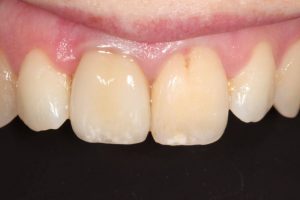

Upper Front Tooth Implant

Both upper front teeth were in a bad way, the upper left one had to be removed as was beyond repair, this was replaced with an implant and a temporary crown on the same day; the upper right front tooth was repaired with a crown. Photos show the result with the definitive crowns after 3 months of treatment.